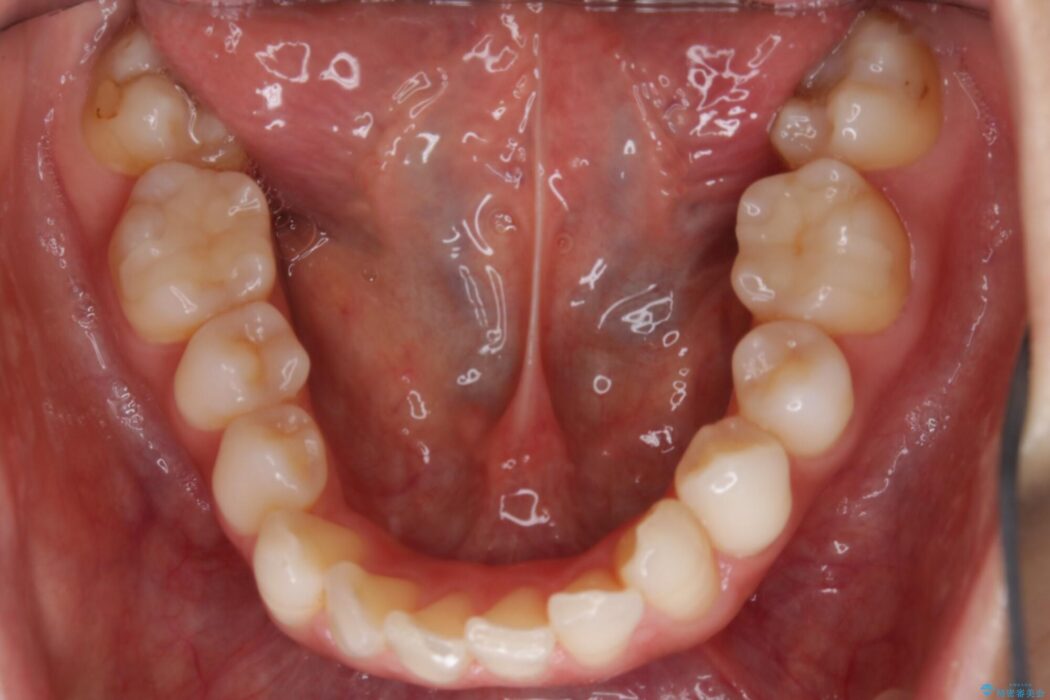

軽度のガタつきと不正咬合が見受けられましたので、インビザラインでの矯正治療を計画しました。

また確認したところ前歯と奥歯にセラミッククラウンで治療した歯があったため、そちらに影響のない範囲内で口腔内全体の噛み合わせが改善されるように歯を動かしていくことになりました。